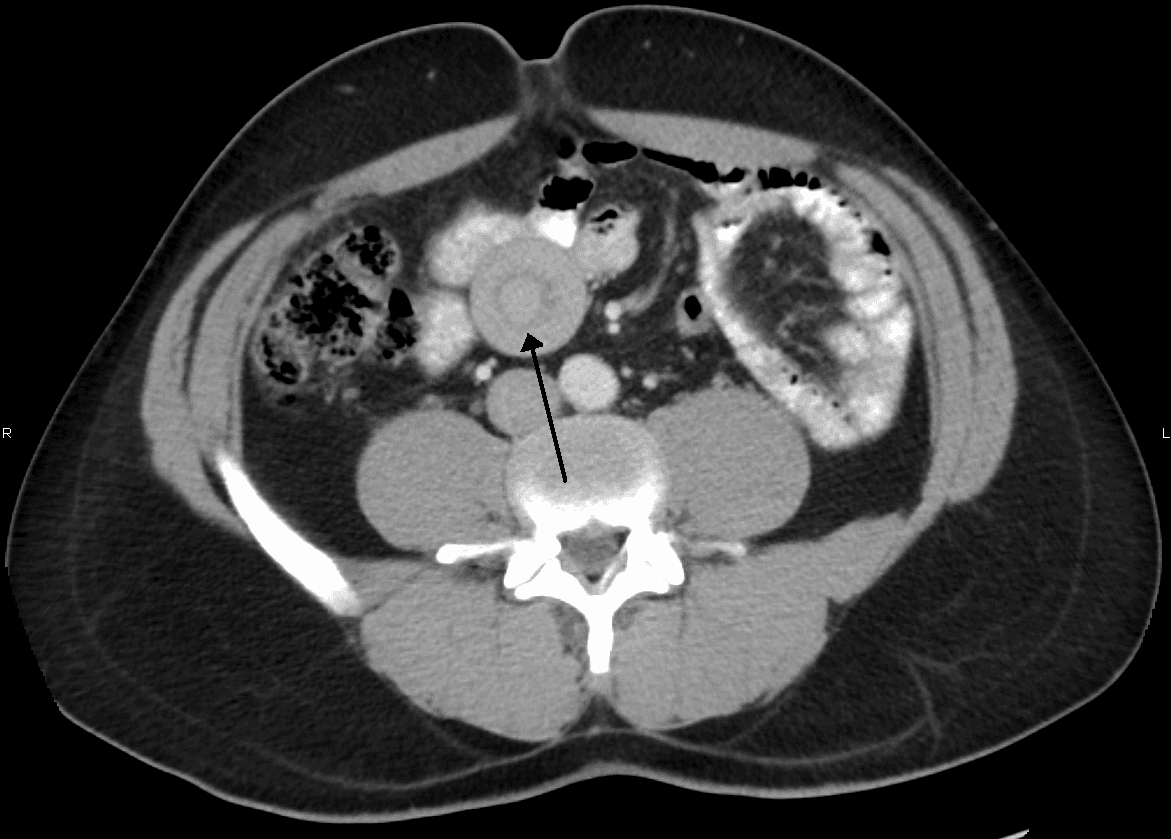

Intussusception is a medical condition in which a part of the intestine folds into the section immediately ahead of it. It typically involves the small bowel and less commonly the large bowel. Symptoms include abdominal pain which may come and go, vomiting, abdominal bloating, and bloody stool. It often results in a small bowel obstruction. Other complications may include peritonitis or bowel perforation. The cause in children is typically unknown; in adults a lead point is sometimes present. Risk factors in children include certain infections, diseases like cystic fibrosis, and intestinal polyps. Risk factors in adults include endometriosis, bowel adhesions, and intestinal tumors. Diagnosis is often supported by medical imaging. In children, ultrasound is preferred while in adults a CT scan is preferred. Intussusception is an emergency requiring rapid treatment. Treatment in children is typically by an enema with surgery used if this is not successful. Dexamethasone may decrease the risk of another episode. In adults, surgical removal of part of the bowel is more often required. Intussusception occurs more commonly in children than adults. In children, males are more often affected than females. The usual age of occurrence is six to eighteen months old. Early symptoms can include periodic abdominal pain, nausea, vomiting (sometimes green in color from bile), pulling legs to the chest area, and intermittent moderate to severe cramping abdominal pain. Pain is intermittent—not because the intussusception temporarily resolves, but because the intussuscepted bowel segment transiently stops contracting. Later signs include rectal bleeding, often with "red currant jelly" stool (stool mixed with blood and mucus), and lethargy. Physical examination may reveal a "sausage-shaped" mass, felt upon palpating the abdomen. Children, or those unable to communicate symptoms verbally, may cry, draw their knees up to their chest, or experience dyspnea (difficult or painful breathing) with paroxysms of pain.